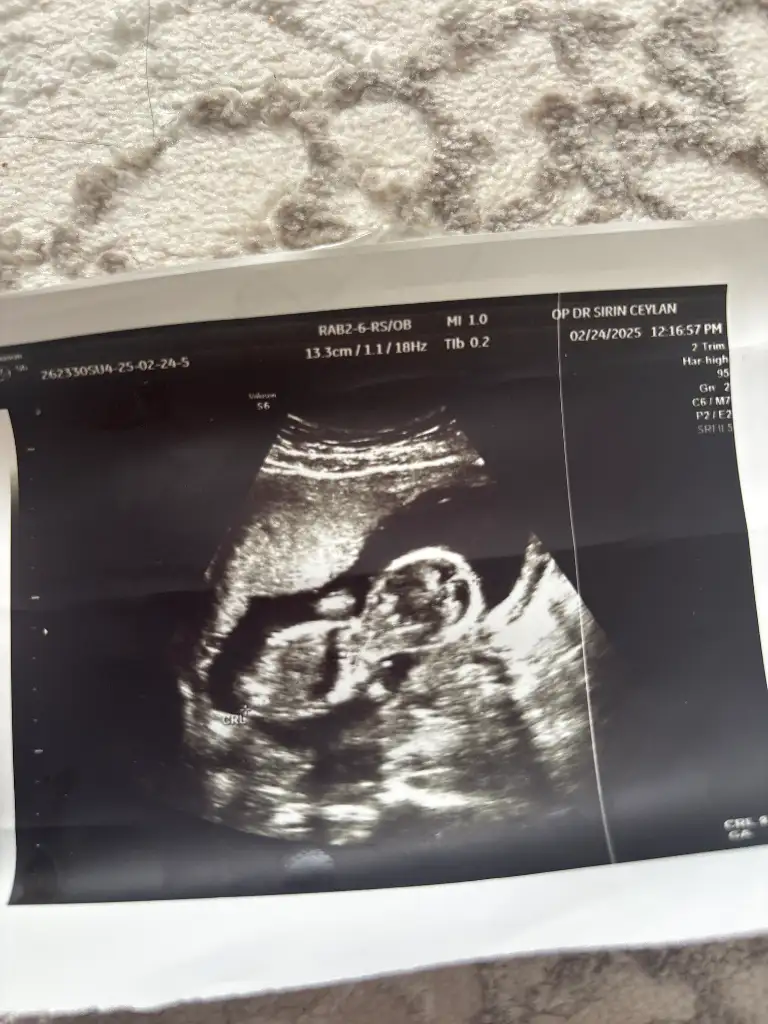

Lütfen bana da bir yorum yapar mısınız. Karından. 13+4 haftalık. İki kızım var erkek olsun istiyorum 🙈